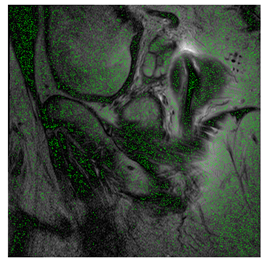

4.3. The Results

In this subsection, we describe three experiments used to measure the performance of the proposed method. The first experiment shows the stegoimage and marks the pixels’ positions that have been modified during the embedding process, as shown in Table 2, Table 3, Table 4, Table 5, Table 6 and Table 7. To make modified pixel positions have a pronounced effect, we set bpp (bit per pixel) rate at 0.05 and 0.025. It can be seen from the results that the proposed local complexity function can distinguish ROI and RONI from most of the medical images, so modified pixels are mainly gathered in RONI. However, it is observed that the proposed local complexity function cannot distinguish between ROI and RONI in the Prostate-MRI database due to the relative complexity of the image. Besides, “Modified BPP” represents the proportion of pixels in the image that have been modified. We observed that the performance of “baboon” in the grayscale standard images database is poor because that image’s pixels are relatively complex. It becomes challenging to select the more embeddable pixels based on the proposed local complexity function. Nevertheless, the modified pixel positions in other grayscale standard images, such as Lena and Barbara, are relatively smooth, verifying that our local complexity function is also applicable to general images.